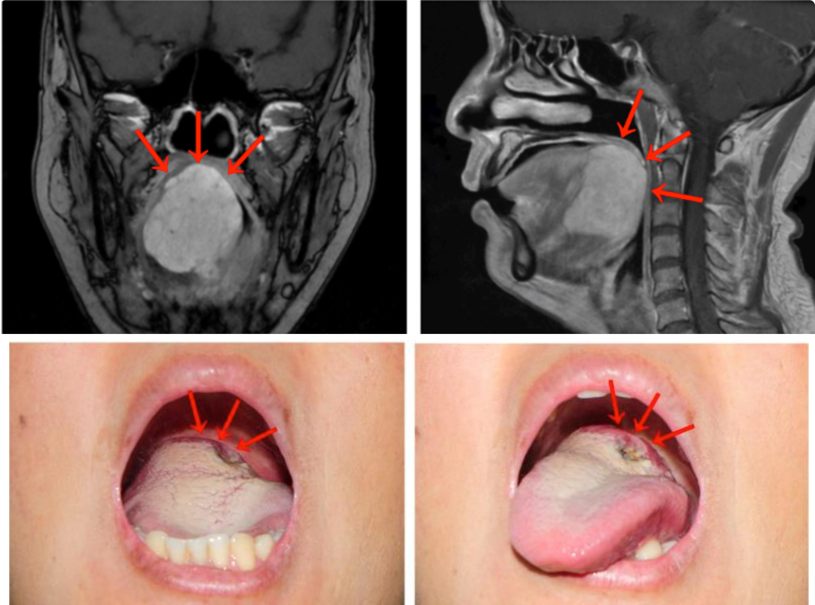

“刘女士的舌根部肿物达到5厘米,几乎占据整个舌根部并向口咽腔突出。中山大学肿瘤防治中心头颈外科门诊宋明主任医师表示,MRI检查提示舌根肿块巨大,范围约47毫米×46毫米×45毫米,向前侵犯部分舌体,向下侵犯部分口底肌群。活检病理诊断考虑为舌根腺样囊性癌 。

面对刘女士舌根部肿物体积巨大的情况,医生陷入了两难:按传统的手术治疗方式,刘女士是需要接受开放性手术的,但这种术式需要将下唇及下颌骨裂开才能暴露并切除舌根肿瘤,对容貌会有一定的影响。

面对才40来岁的刘女士,医生建议她采用经口机器人手术。手术仅用时90分钟,出血量不足50毫升,成功将舌根肿瘤完整切除,并保证足够的安全边界,而且无需进行气管切开术。